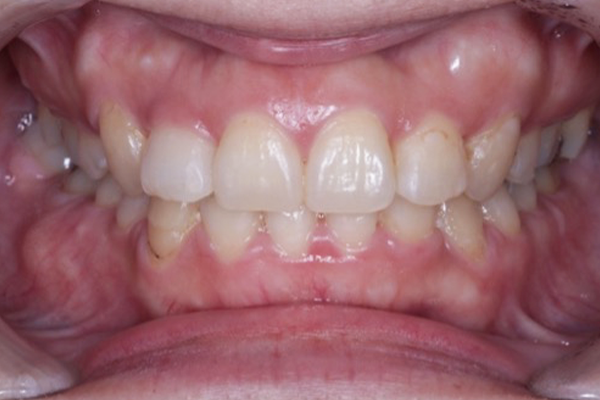

1.口腔内写真・顔貌写真の撮影

お口の中の写真と、正面・横顔の写真を撮影します。

これは単なる記録ではなく、歯並びと顔全体のバランスを分析するために欠かせない資料です。

治療前後の比較にも活用でき、患者さま自身が変化を実感しやすくなるメリットもあります。